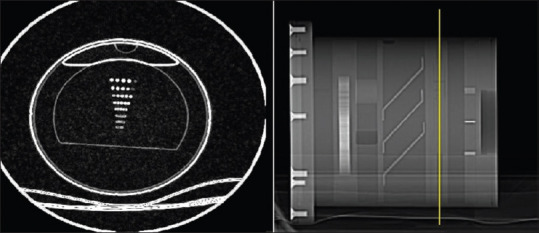

Methods: The body mass measurement device phantom was repeatedly scanned by changing the scan parameters. To analyze the image quality, software-based and observer-based evaluations were employed. To study the effect of scan parameters such as slice thickness and reconstruction filter on image quality and radiation dose, the structural equation modeling was used.